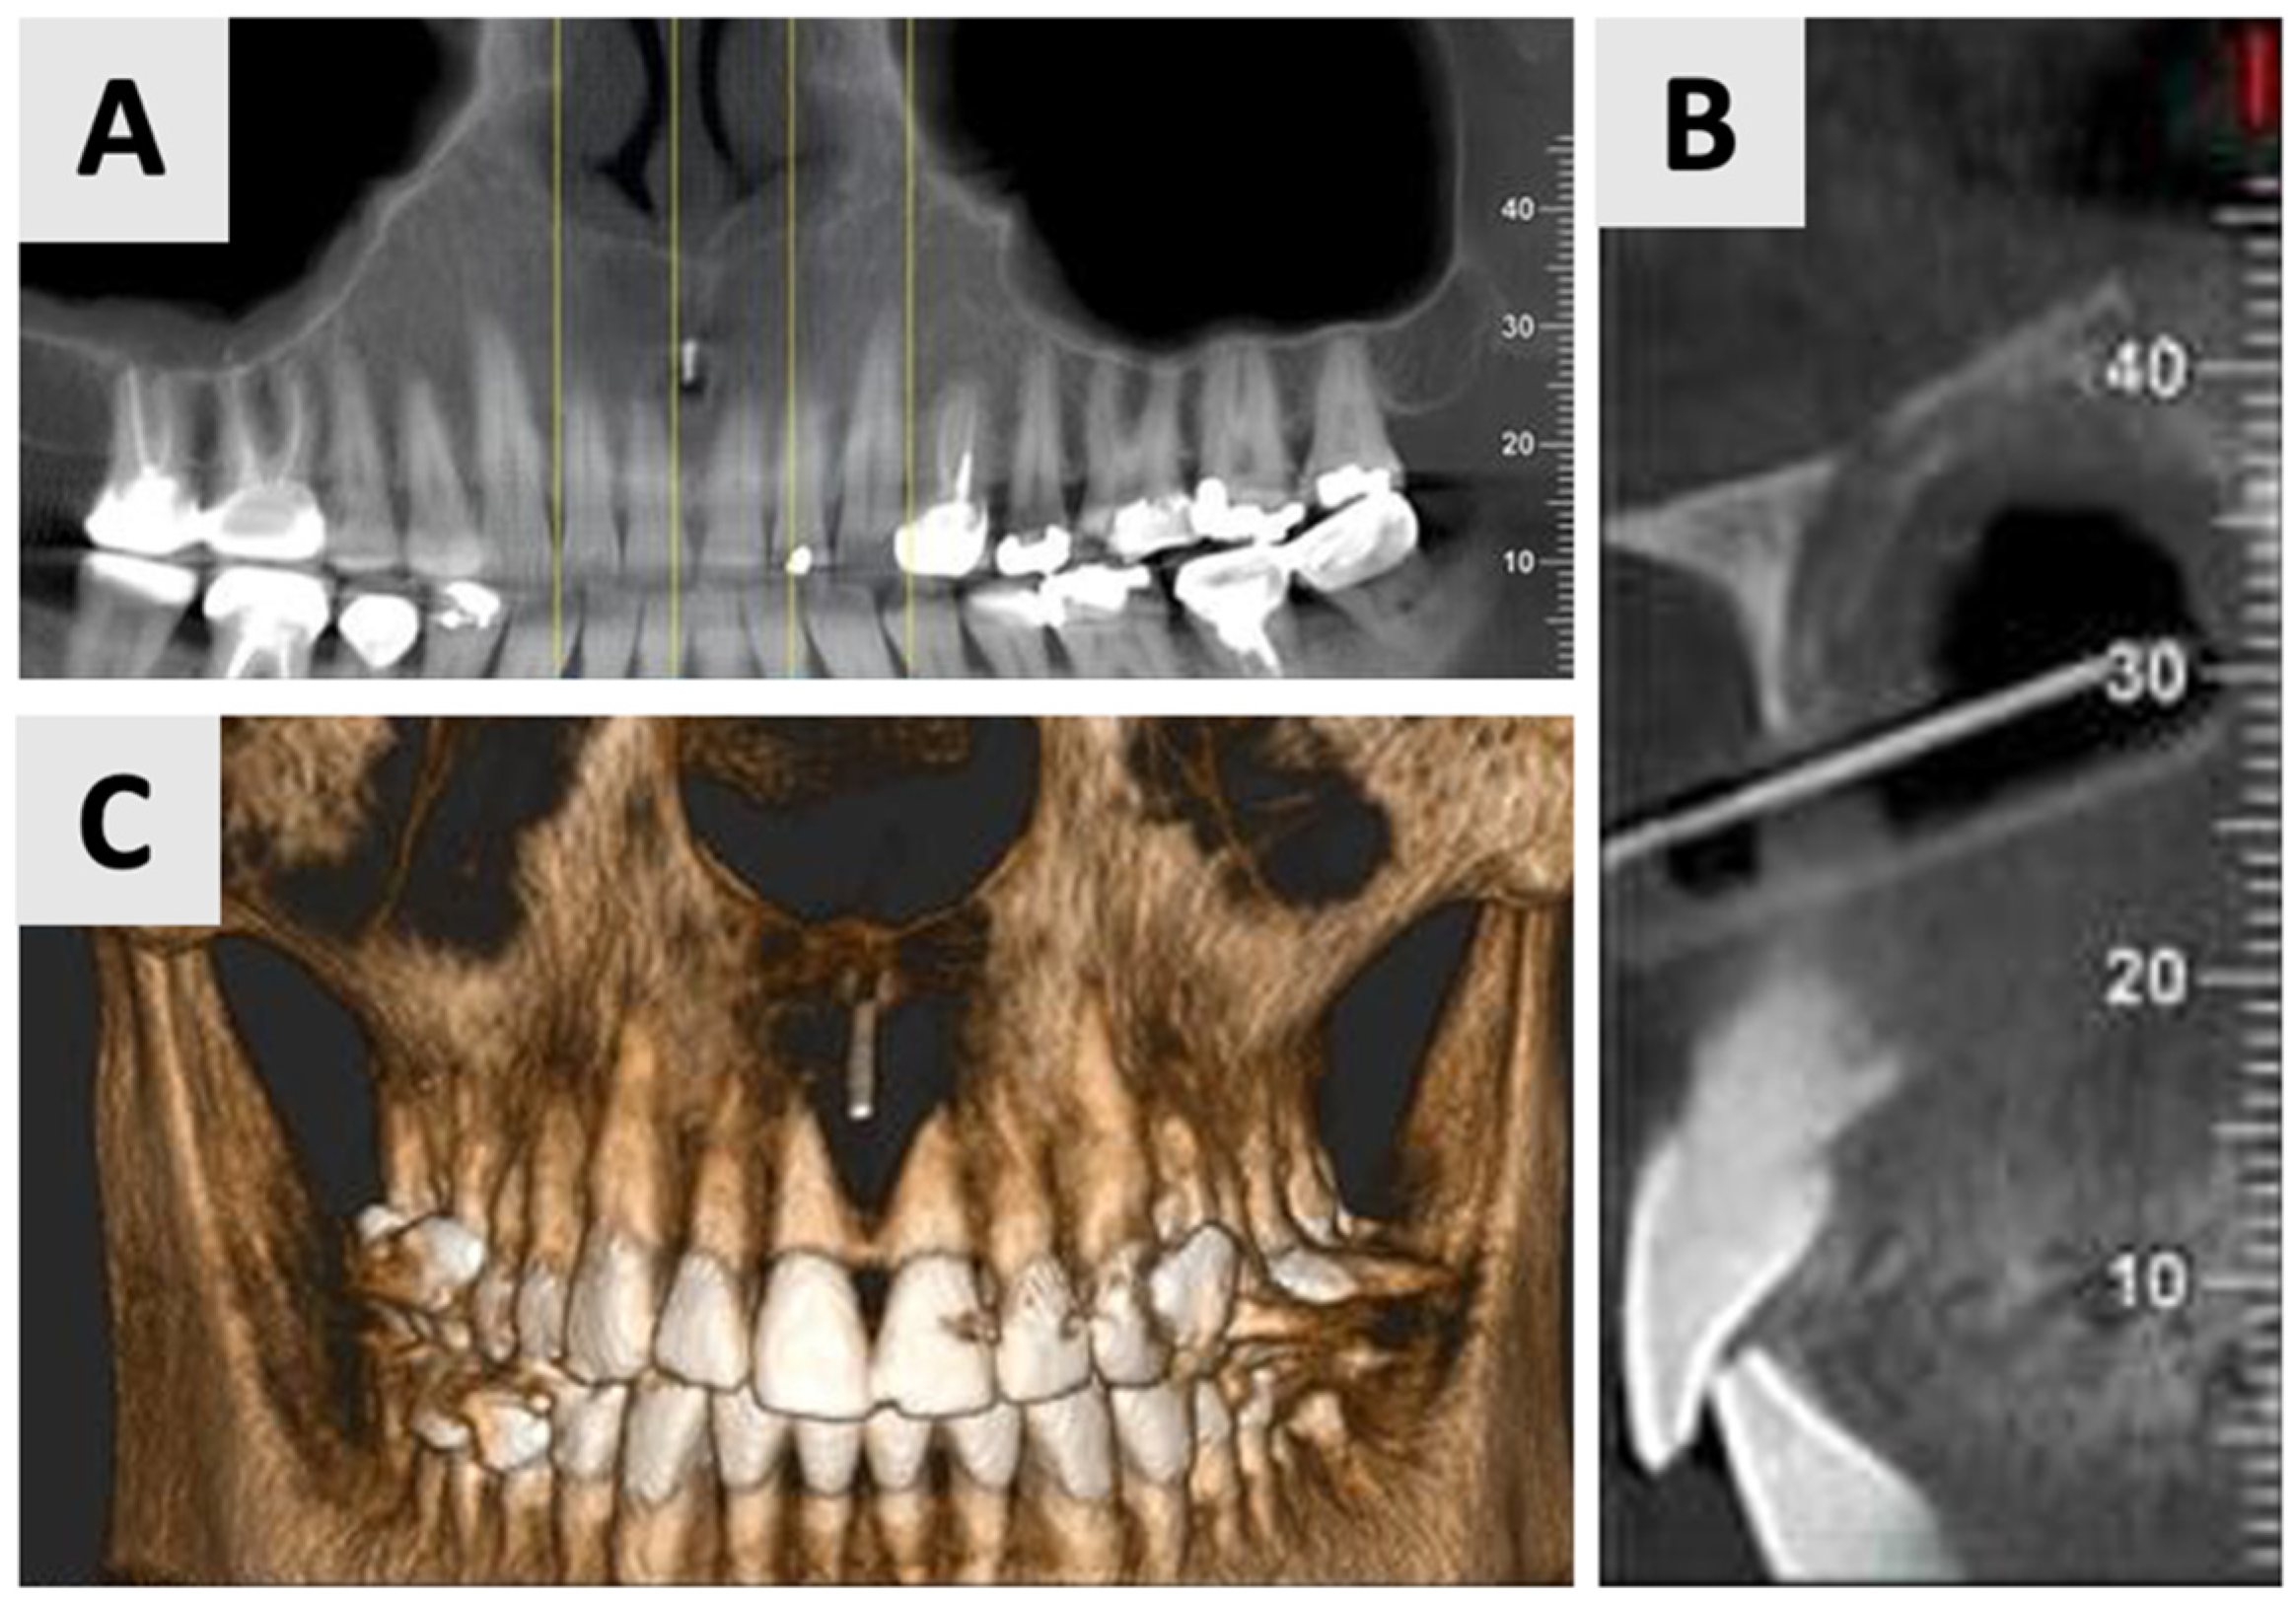

Cone Beam Computed Tomography (CBCT) was performed using the NewTom GO 2D/3D® system (NewTom, Verona, Italy). Imaging was performed to assess the extent and characteristics of the lesion (Figure 1). The CBCT revealed a unilocular hypodense area palatal to the anterior four maxillary teeth, absence of palatal bony walls and intact buccal bony frame. Lesion dimensions were 17 mm (mesiodistal) × 15 mm (buccolingual) × 21 mm (height). These radiographic findings are consistent with the characteristics of a radicular cyst, which typically presents as a well-defined, unilocular radiolucency associated with the apex of a non-vital tooth. The absence of palatal bony walls suggests potential expansion or erosion of the palatal cortex.

Figure 1.

Radiographic images of the cyst at initial visit before marsupialization. (A) Axial, and (B) coronal views of the cyst center. Measurements indicate cyst dimensions: mesiodistal 17 mm × buccolingual 15 mm × height 21 mm.